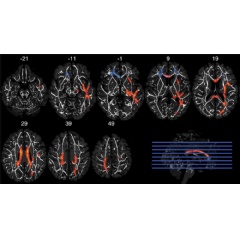

Two MRI techniques—diffusion tensor imaging (DTI) and functional MRI (fMRI)—were used to examine 61 of the former players. MRI data from the other three players were excluded due to excessive movement or inability to complete the MRI exam. DTI was used to analyze white matter structural integrity, while fMRI was used to assess brain function while the players performed a memory task.

“While DTI and fMRI have been used previously in the field of concussion research, we are among the first to combine the two techniques,” said co-author Michael Clark, medical student at UNC-Chapel Hill. “We were interested in how white matter and the ability to recruit brain resources to complete a memory task might be affected by head impact exposure in terms of career length and the position played. By using two different and complementary types of MRI, we were able to see the relationship between structure and function, both of which are affected by head impact exposure.”

The non-speed players with a history of recurrent concussion had reduced integrity in the frontal white matter and lower measure of activation during the fMRI task than those with one concussion or less. This was not the case for the speed players.

The interactions observed between concussion histories and playing positions suggest there may be important differences in the mechanisms of injury between speed and non-speed players. The magnitude, location and frequency of head impacts in football differ by position. Offensive backs experience impacts at greater acceleration. Linemen, however, tend to experience a greater overall frequency of impacts, and have the greatest proportion of impacts to the front of the helmet. The high proportion of frontal impacts experienced by non-speed players may result in more localized damage to frontal white matter tracts as compared to the more variable impact locations experienced by speed position players.